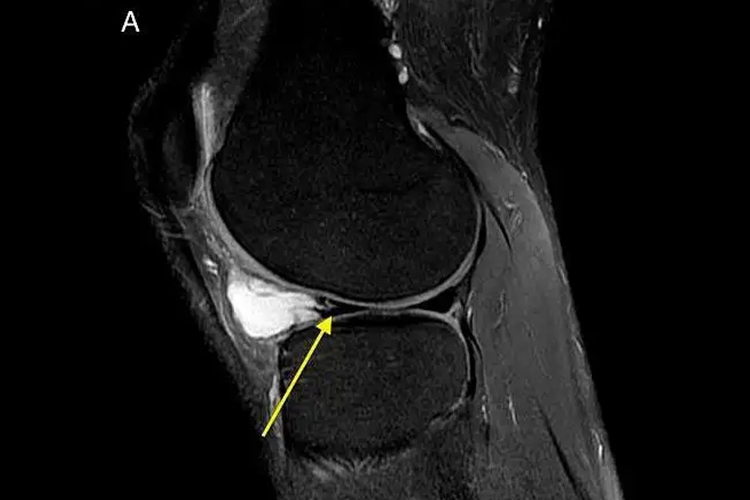

半月板囊肿典型MRI显示半月板外缘与关节囊之间出现圆形囊性病变,呈T1等或稍低信号,T2明显高信号,一般无分离,常与水平状半月板撕裂外缘相连。